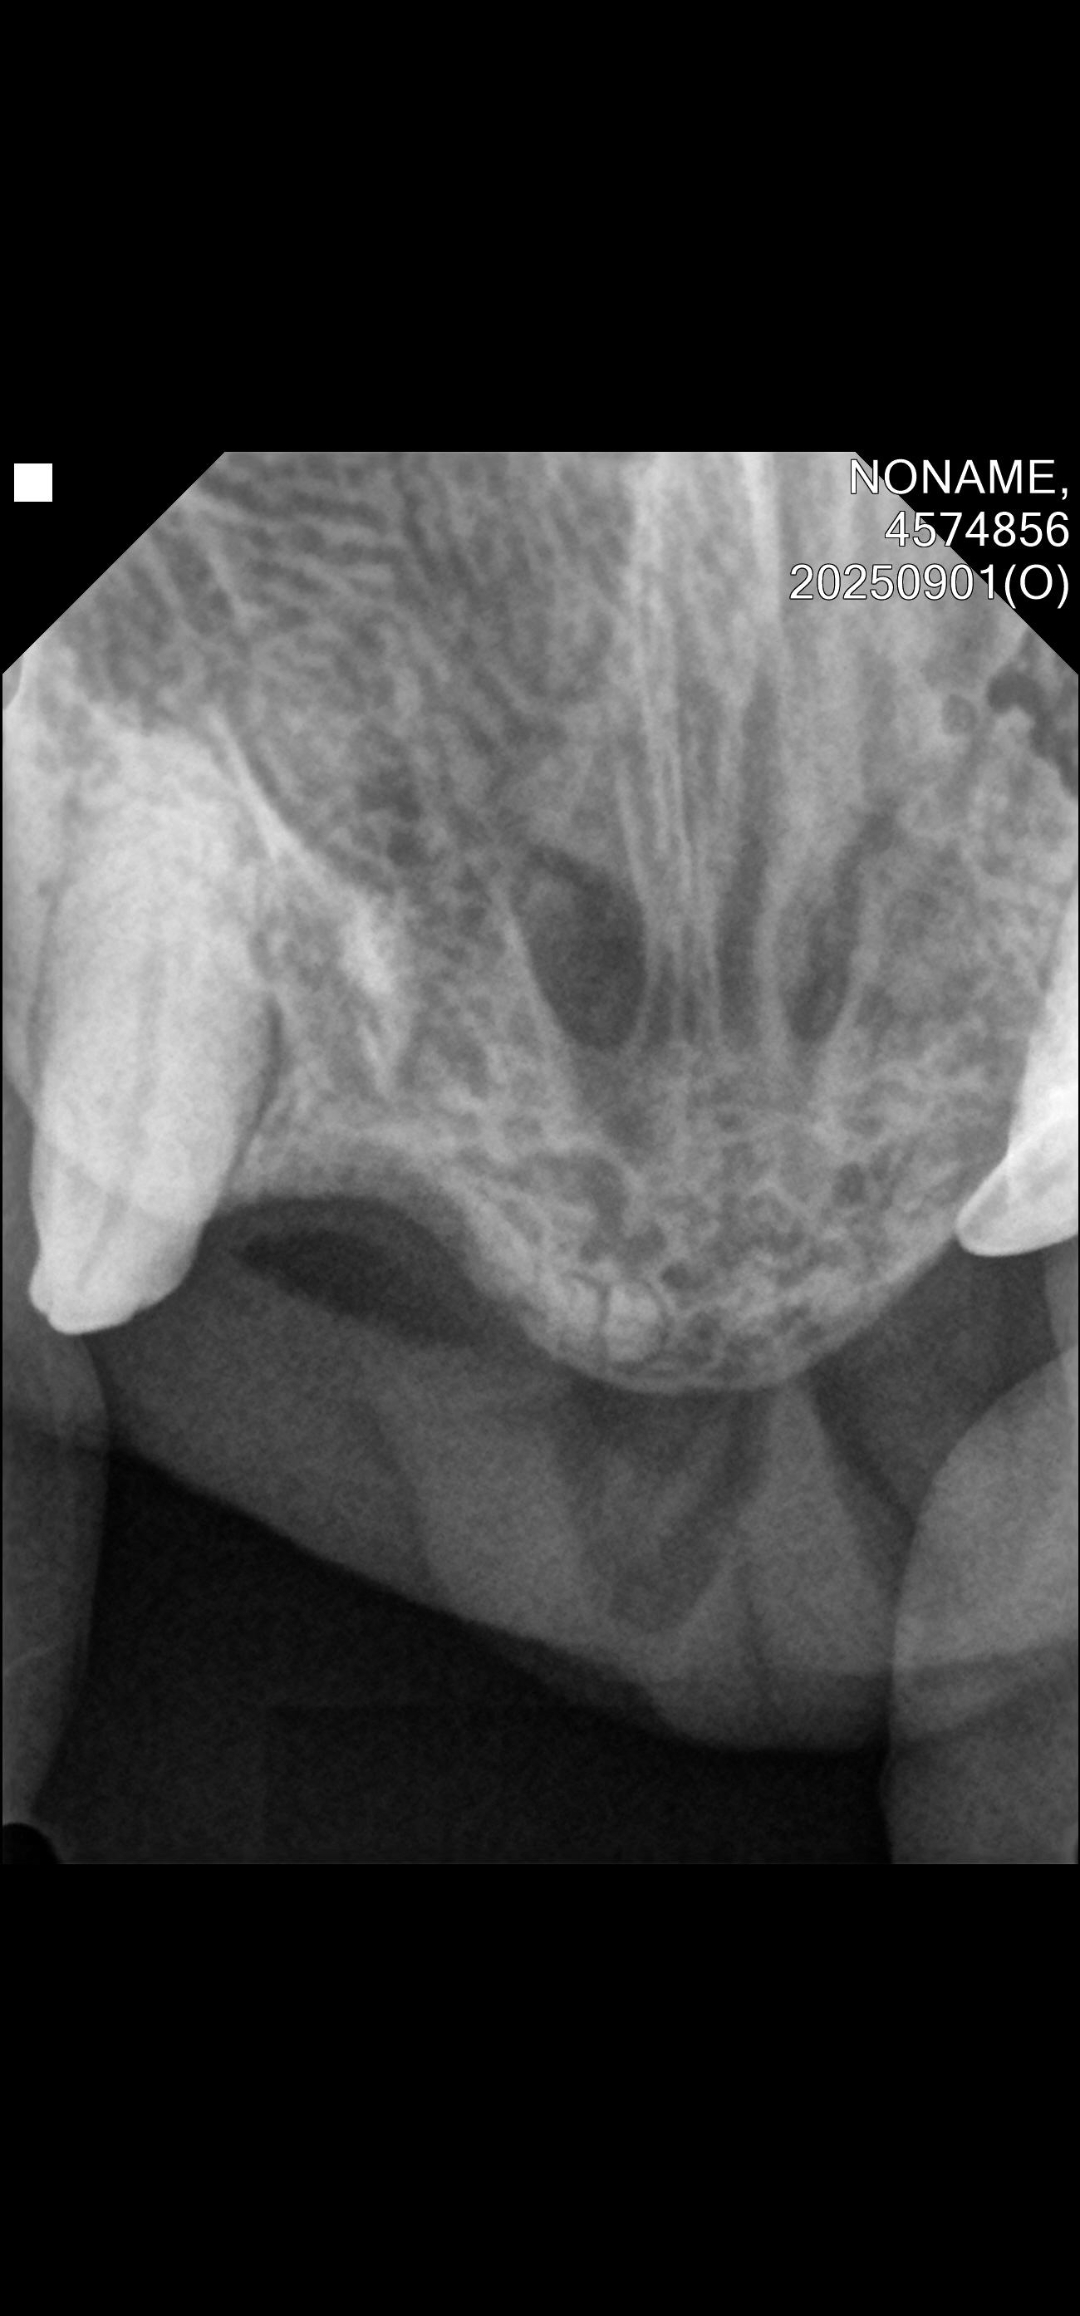

| 대상묘 병명 | 칼리시 치아흡수병변으로 인한 구내염 |

| 치료과정 | 8월31일에 구조하여 병원에 데려갔고 병원에서 발치 수술을 진행했습니다. 발치 당시 혈액검사 상으로 빈혈 수치가 있고 황달이 있어서 수술 후에 2주 입원시켰습니다. 앞에 송곳니는 치아흡수병변 소견도 있고 현재로는 염증이 없거나 살짝 있는 걸로 보여 발치하지 않고 어금니와 다른 이빨들만 발치했습니다. 송곳니를 제외한 앞니는 이미 빠져있었고 송곳니도 치아흡수병변 증상으로 발치할 경우 턱뼈가 부러질 수도 있어서 발치를 하지 않으셨다고 합니다. 나이가 들면서 치주질환과 충치가 생긴 줄 알았는데 칼리시로 인한 구내염이고 목구멍과 혀에까지 궤양이 있었습니다. 목구멍은 레이저치료를 했으나 혀는 레이저 치료가 위험해서 하지 못 했습니다. 수술 후에 잘 먹으면 황달은 없어진다고 해서 입원시켜서 상태를 지켜봤는데 다행이 잘 먹고 잘 잤다고 합니다. 염증이 너무 심해서 입원해 있을 동안 계속 투약했습니다. 2주 입원 후에 방사하려고 했으나 아직 너무 말라있고 았던 기간이 오래되기도 해서 좀 더 데리고 있기로 결정했습니다. 기력이 다시 떨어지는 것 같기도 하고 다시 잘 안 먹으려고 하기도 해서 2주간 실내에서 더 케어하면서 상태를 관찰한 후에 방사하려고 합니다. 스테로이드제제를 2주 이상 투약해서 휴지가를 가졌다가 다시 먹여보려고 합니다. |